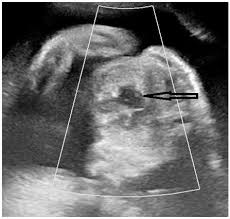

Neste caso, para que a Corte tenha uma noção mais exata do que estamos falando. Imagine o feto flutuando encerrado no líquido amniótico. O profissional responsável deverá, sem sequer haver anestesia, alcançar uma veia de seu corpo, ou diretamente o coração, para tentar injetar as drogas a serem utilizadas.

Como dito, o feto está flutuando, não estando em posição fixa, o que leva o profissional responsável a penetrar-lhe inúmeras vezes com mecanismo perfurante até finalmente localizar a veia a ser injetada ou o coração.

O feto não está anestesiado e, obviamente, lembremos que já é um ser humano, em período perinatal, não irá ser alvejado pela perfuração facilmente, mexendo-se incansavelmente na tentativa de se livrar das punções havidas e da dor. Esse procedimento não é rápido, não é simples e, como facilmente perceptível, bastante doloroso e traumático ao ser humano já formado que ali se encontra![2]